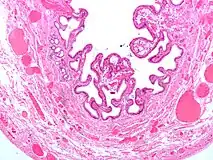

Micrograph of cholesterolosis of the gallbladder -

The name strawberry gallbladder comes from the typically stippled appearance of the mucosal surface on gross examination, which resembles a strawberry. Cholesterolosis results from abnormal deposits of cholesterol esters in macrophages within the lamina propria (foam cells) and in mucosal epithelium. The gallbladder may be affected in a patchy localized form or in a diffuse form. The diffuse form macroscopically appears as a bright red mucosa with yellow mottling (due to lipid), hence the term strawberry gallbladder. It is not tied to cholelithiasis (gallstones) or cholecystitis (inflammation of the gallbladder).[2]